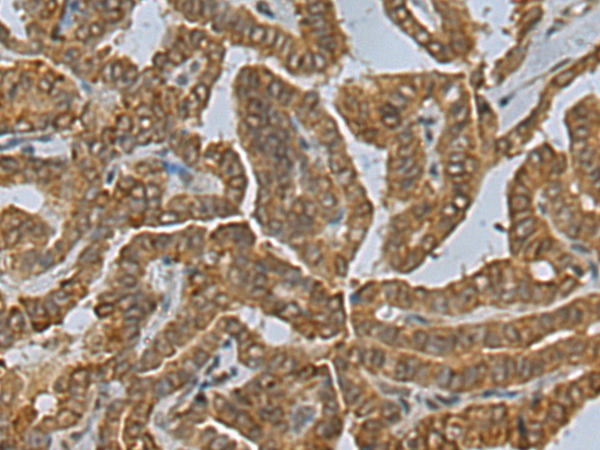

分类: 科研抗体货号: P09869别名:应用: IHC反应种属: Human